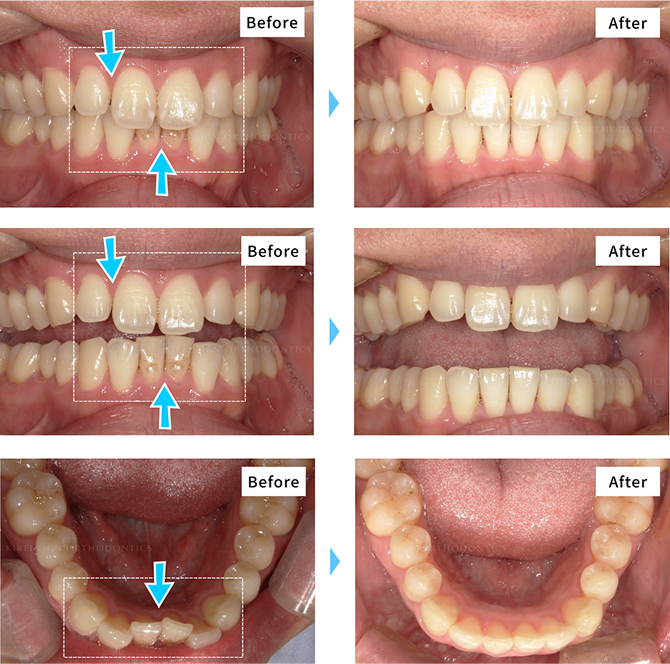

矯正治療の症例

キレイラインを10回実施

- [ 治療期間 ] 約10ヶ月半

- [ 治療費用 ] 420,000円

(税込462,000円)

- [再診料] (6回 18,000円 (税込19,800円)

- [追加治療] なし

※効果には個人差があります。

※補綴・治療の費用は各提携クリニックによって異なります。